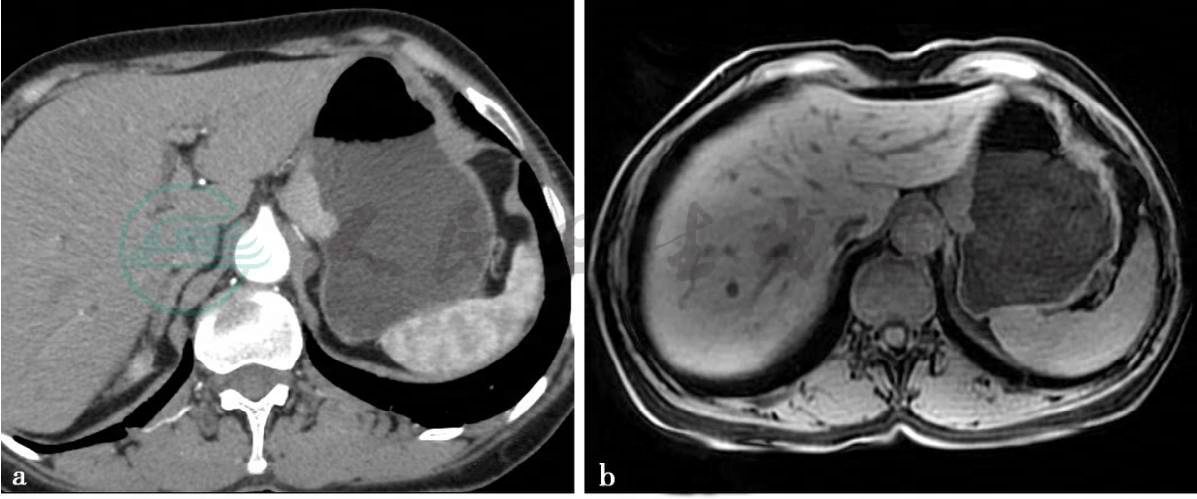

病例7:CT增强扫描及MRI平扫及弥散加权图(贲门胃底癌)。

图1 图1a,CT增强静脉期图。图1b~d,分别为轴位T1WI,T2WI及DWI图。贲门胃底可见软组织肿块,轻度强化,MRI上呈稍长T1,稍长T2信号,DWI上为高信号